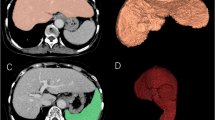

To assess the utility of a machine-learning approach for predicting liver function based on technetium-99 m-galactosyl serum albumin (99mTc-GSA) single photon emission computed tomography (SPECT)/CT.

One hundred twenty-eight patients underwent a 99mTc-GSA SPECT/CT-based liver function evaluation. All were classified into the low liver-damage or high liver-damage group. Four clinical (age, sex, background liver disease and histological type) and 8 quantitative 99mTc-GSA SPECT/CT features (receptor index [LHL15], clearance index [HH15], liver-SUVmax, liver-SUVmean, heart-SUVmax, metabolic volume of liver [MVL], total lesion GSA [TL-GSA, liver-SUVmean × MVL] and SUVmax ratio [liver-SUVmax/heart-SUVmax]) were obtained. To predict high liver damage, a machine learning classification with features selection based on Gini impurity and principal component analysis (PCA) were performed using a support vector machine and a random forest (RF) with a five-fold cross-validation scheme. To overcome imbalanced data, stratified sampling was used. The ability to predict high liver damage was evaluated using a receiver operating characteristic (ROC) curve analysis.

Yoshida M, Beppu T, Shiraishi S, et al (2015) (99m)Tc-GSA SPECT/CT fused images for assessment of hepatic function and hepatectomy planning. Ann Transl Med 3:17

Tokorodani R, Sumiyoshi T, Okabayashi T, et al (2019) Liver fibrosis assessment using 99 mTc-GSA SPECT/CT fusion imaging. Jpn J Radiol 37:315-320